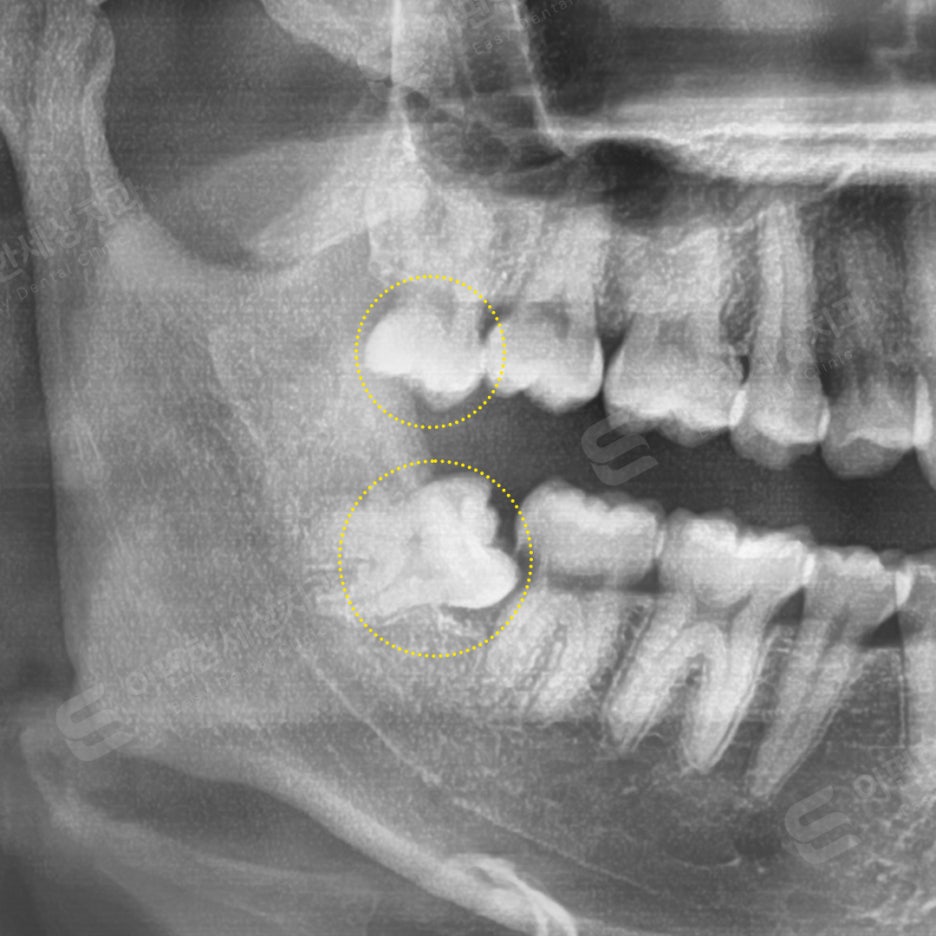

촬영 일자 24.02.16

인터넷 검색 후 내원, 당일 발치 케이스

#48 완전매복 발치

치근단 신경이 닿아서

CT 촬영 후 발치

#18 일반 발치